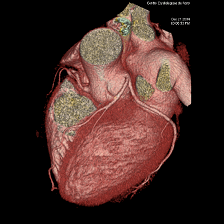

このボリュームCTにより早期発見から早期治療へつなげることが可能となり、心臓カテーテル検査の代替としても期待されます。

一部の症例以外では、従来の心臓カテーテル検査なしに血管狭窄の評価が可能であり、万が一、心筋梗塞になられた場合でも治療後の経過観察の心臓カテーテル検査は不要となります。

①安定した心臓撮影 : 心臓を5秒にて撮影(従来のマルチスライスCTでは約20秒間撮影)